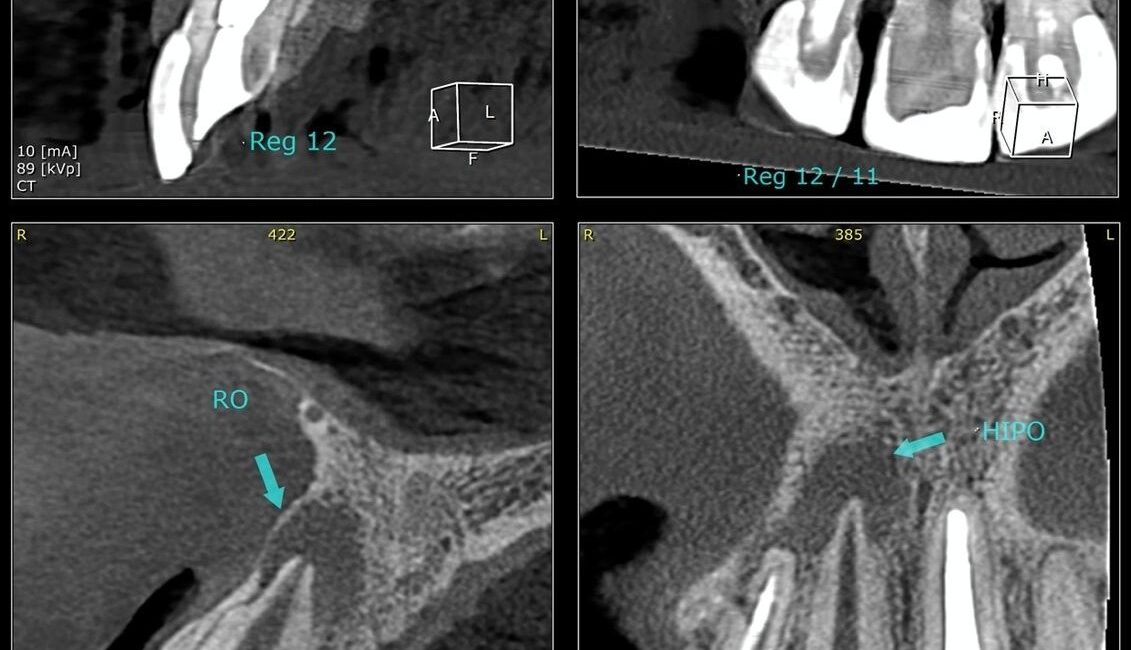

O diagnóstico da necessidade de uma apicectomia se baseia na avaliação clínica e nos exames de imagem. A radiografia e a tomografia computadorizada visualizam com precisão a extensão da lesão.

No caso citado, os exames mostraram claramente a presença de uma lesão no ápice do dente, tanto na região lateral quanto central da raiz, confirmando a necessidade de intervenção cirúrgica.